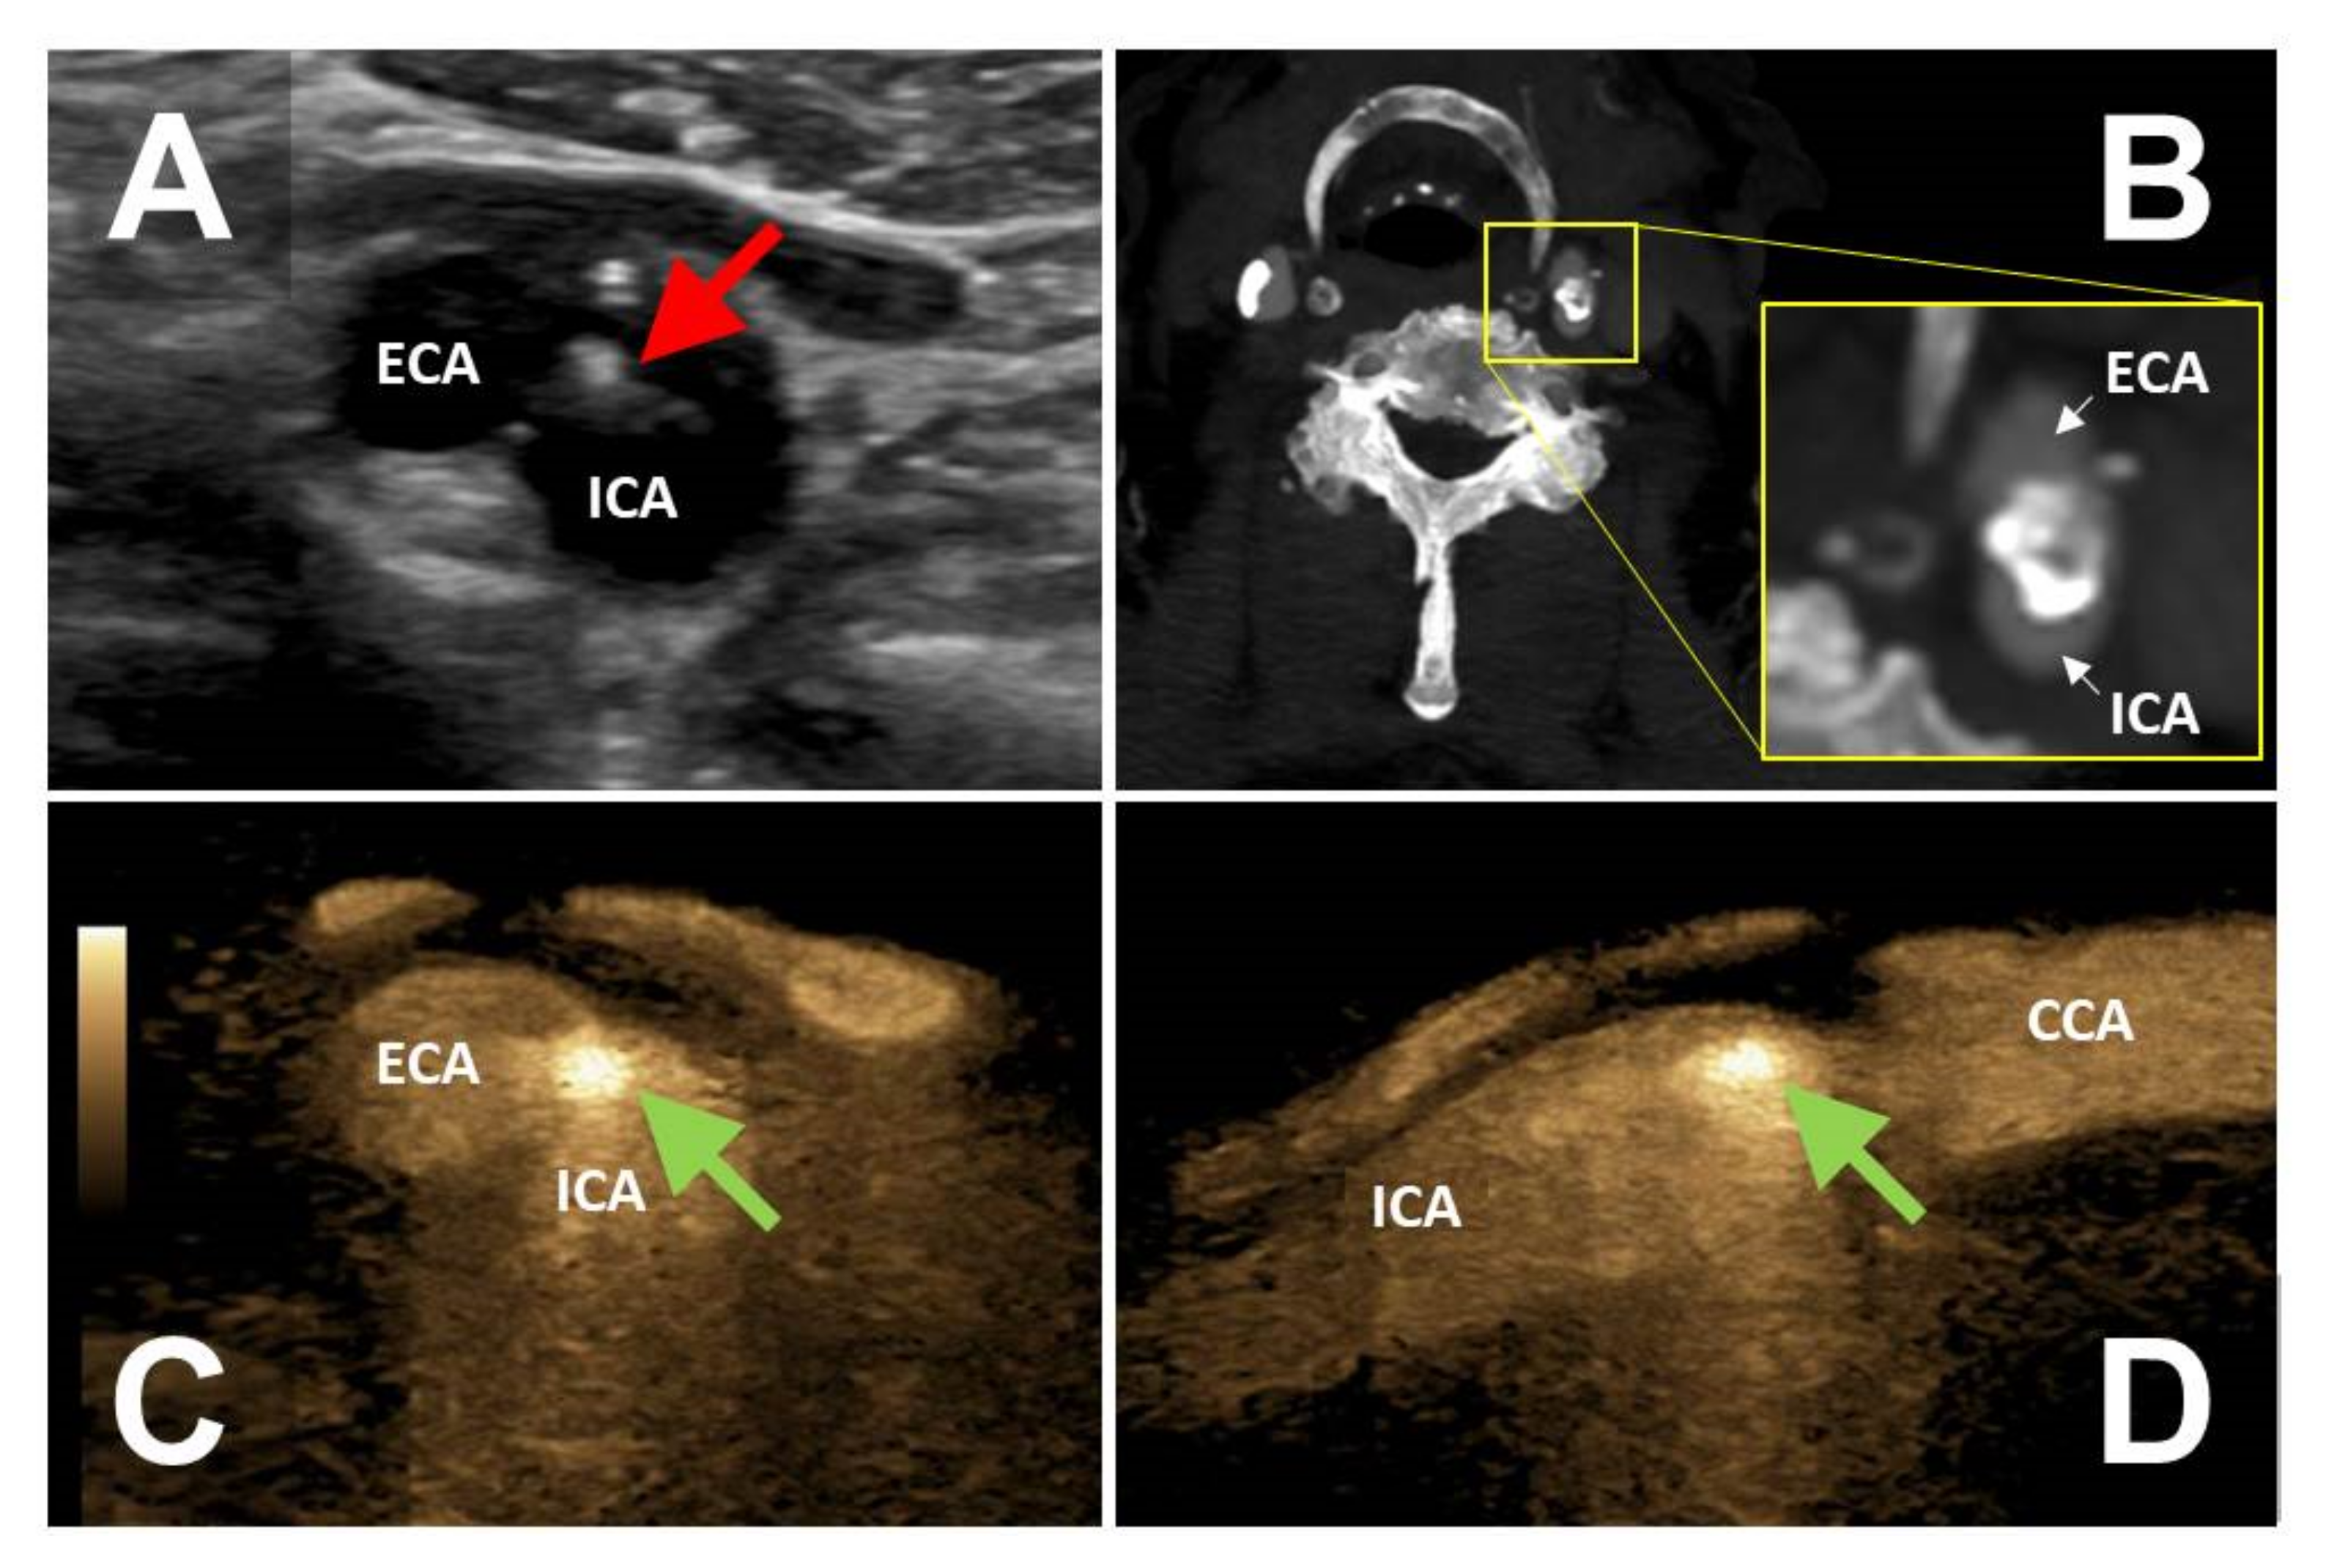

The FLS was detected in peripheral arteries of 10 patients (seven men and three women), including the femoral arteries in six patients, the carotid arteries in two patients, and the brachiocephalic artery and axillary artery in one patient, respectively. In two patients, the FLS-positive lesion was considered the most probable source of symptomatic arterial embolism. One female patient with right-sided retinal artery occlusion had a large arteriosclerotic plaque with WAFAS of the brachiocephalic trunk. Another male patient suffered from left hand ischemia due to an arterial embolism originating from a stenotic arteriosclerotic lesion of the ipsilateral axillary artery containing a WAFAS. It is worthy of note that in six patients the FLS was detected after revascularization procedures (two FLS of the common femoral artery which had been used as an access vessel for endovascular procedures, three FLS of the superficial femoral artery after endovascular recanalization, and one FLS after carotid endarterectomy). Two FLS were found incidentally in patients with severe calcifying arteriosclerosis (origin of the internal carotid artery and of the superficial femoral artery, respectively).

3.5. Clinical Impact of the FLS

In six patients the FLS had a direct, additional impact on further patient management, including the initiation of anticoagulation in four patients and the initiation of antiplatelet therapy in two patients. One asymptomatic patient with a FLS corresponding to WAFAS adherent to a mid-grade internal carotid artery stenosis (Figure 3) underwent successful carotid endarterectomy. The above-mentioned patient with recurrent popliteal artery embolism originating from a floating intraluminal thrombus located in the EVAR limbs underwent endovascular re-lining of the prosthesis with covered stent grafts.

Figure 3. Large arteriosclerotic plaque (red arrow) resulting in ostial mid-grade stenosis of the internal carotid artery (panel A). CTA reveals calcification of the plaque but no evidence of WAFAS (panel B). WAFAS was discovered by BFl (FLS, green arrows) in the transversal (panel C) and longitudinal (panel D) plane. CTA, computed tomography angiography; WAFAS, wall-adherent, floating arterial structure; BFl, B-Flow; FLS, flashlight sign; ECA, external carotid artery; ICA, internal carotid artery; CCA, common carotid artery.